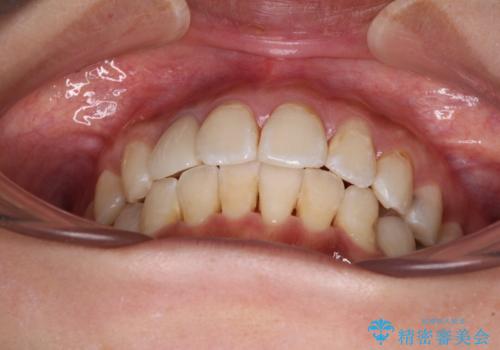

デコボコで磨きにくい前歯をスッキリと インビザライン矯正

歯磨きしやすくなるとともに、飛び出していた前歯も引っ込めて整えることができました。